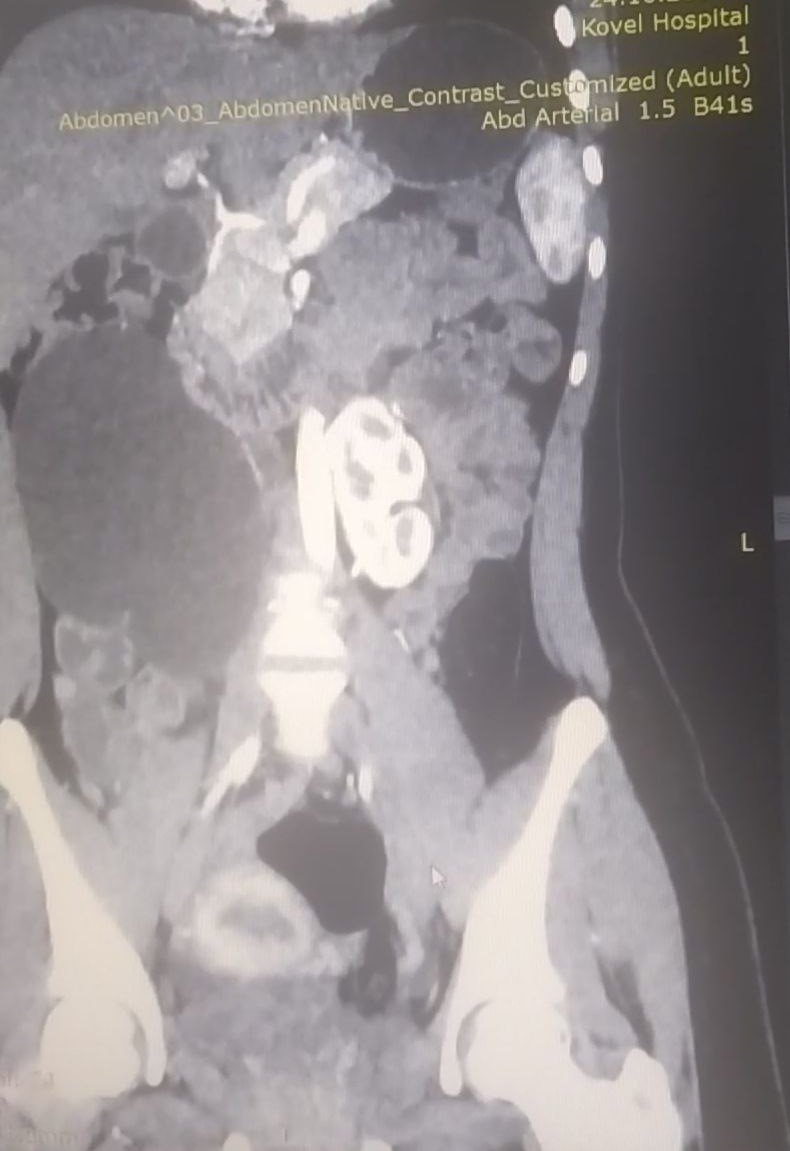

Вперше у Ковелі провели унікальну урологічну операцію 17-річній пацієнтці, яка мала вроджену ваду сечовидільної системи – підковоподібну нирку (зрощення двох нирок). Стан її здоров’я погіршувався упродовж багатьох років, аж поки права половина підковоподібної нирки перестала функціонувати.

Хвору доставили в лікарню у важкому стані з вираженим больовим синдромом та наявністю гіпертонічного кризу. Через звуження у сечоводі та ускладнення відтоку сечі, об’єм рідини в нирці сягнув критичного рівня. А збільшення її розмірів стало помітним навіть зовні.

Лікарі діагностували термінальний гідронефроз із наслідками, гідронефротичну трансформацію правої половини підковоподібної нирки, вторинну артеріальну гіпертензію.